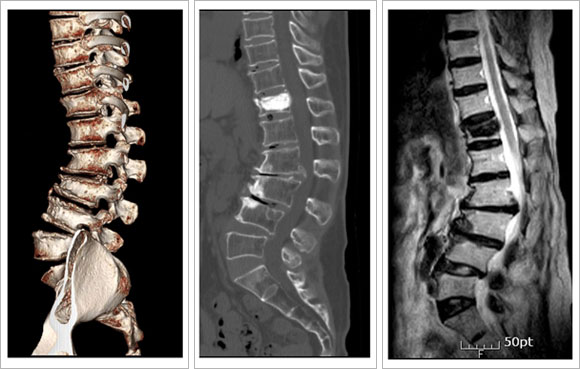

3) ÅðÇ༺

ôÃß Èĸ¸ º¯Çü

| |

|

-

3D CT ¹× MRI : ¿äÃß 2, 3¹ø¿¡ ½ÉÇÑ Ã´Ãß°ü ÇùÂø ¹× ¿äÃß Èĸ¸ º¯Çü º¸ÀÓ.